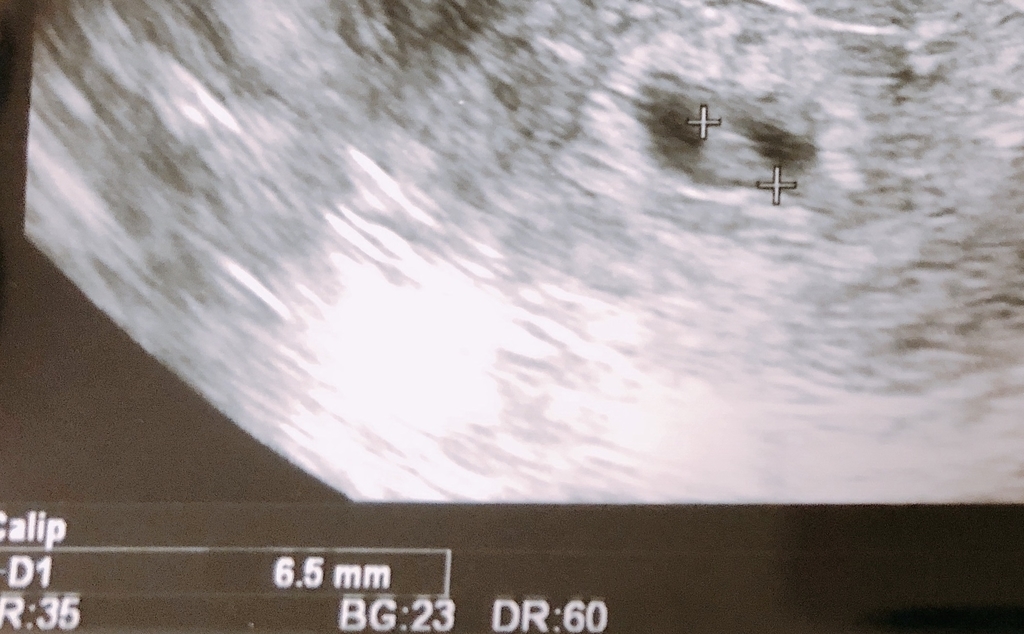

心拍確認は、初めての経験でした。

心臓がピコピコと動いていて、もっと感動するのかなと思ったのですが、意外に冷静な自分がいて驚きました。

まあ、小さいと言われたから、またダメになるのかなぁ。と思って心を守っている自分がいるのかもです。